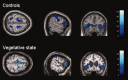

Recent studies on spontaneous fluctuations in the functional MRI blood oxygen level-dependent (BOLD) signal in awake healthy subjects showed the presence of coherent fluctuations among functionally defined neuroanatomical networks. However, the functional significance of these spontaneous BOLD fluctuations remains poorly understood. By means of 3 T functional MRI, we demonstrate absent cortico-thalamic BOLD functional connectivity (i.e. between posterior cingulate/precuneal cortex and medial thalamus), but preserved cortico-cortical connectivity within the default network in a case of vegetative state (VS) studied 2.5 years following cardio-respiratory arrest, as documented by extensive behavioral and paraclinical assessments. In the VS patient, as in age-matched controls, anticorrelations could also be observed between posterior cingulate/precuneus and a previously identified task-positive cortical network. Both correlations and anticorrelations were significantly reduced in VS as compared to controls. A similar approach in a brain dead patient did not show any such long-distance functional connectivity. We conclude that some slow coherent BOLD fluctuations previously identified in healthy awake human brain can be found in alive but unaware patients, and are thus unlikely to be uniquely due to ongoing modifications of conscious thoughts. Future studies are needed to give a full characterization of default network connectivity in the VS patients population.